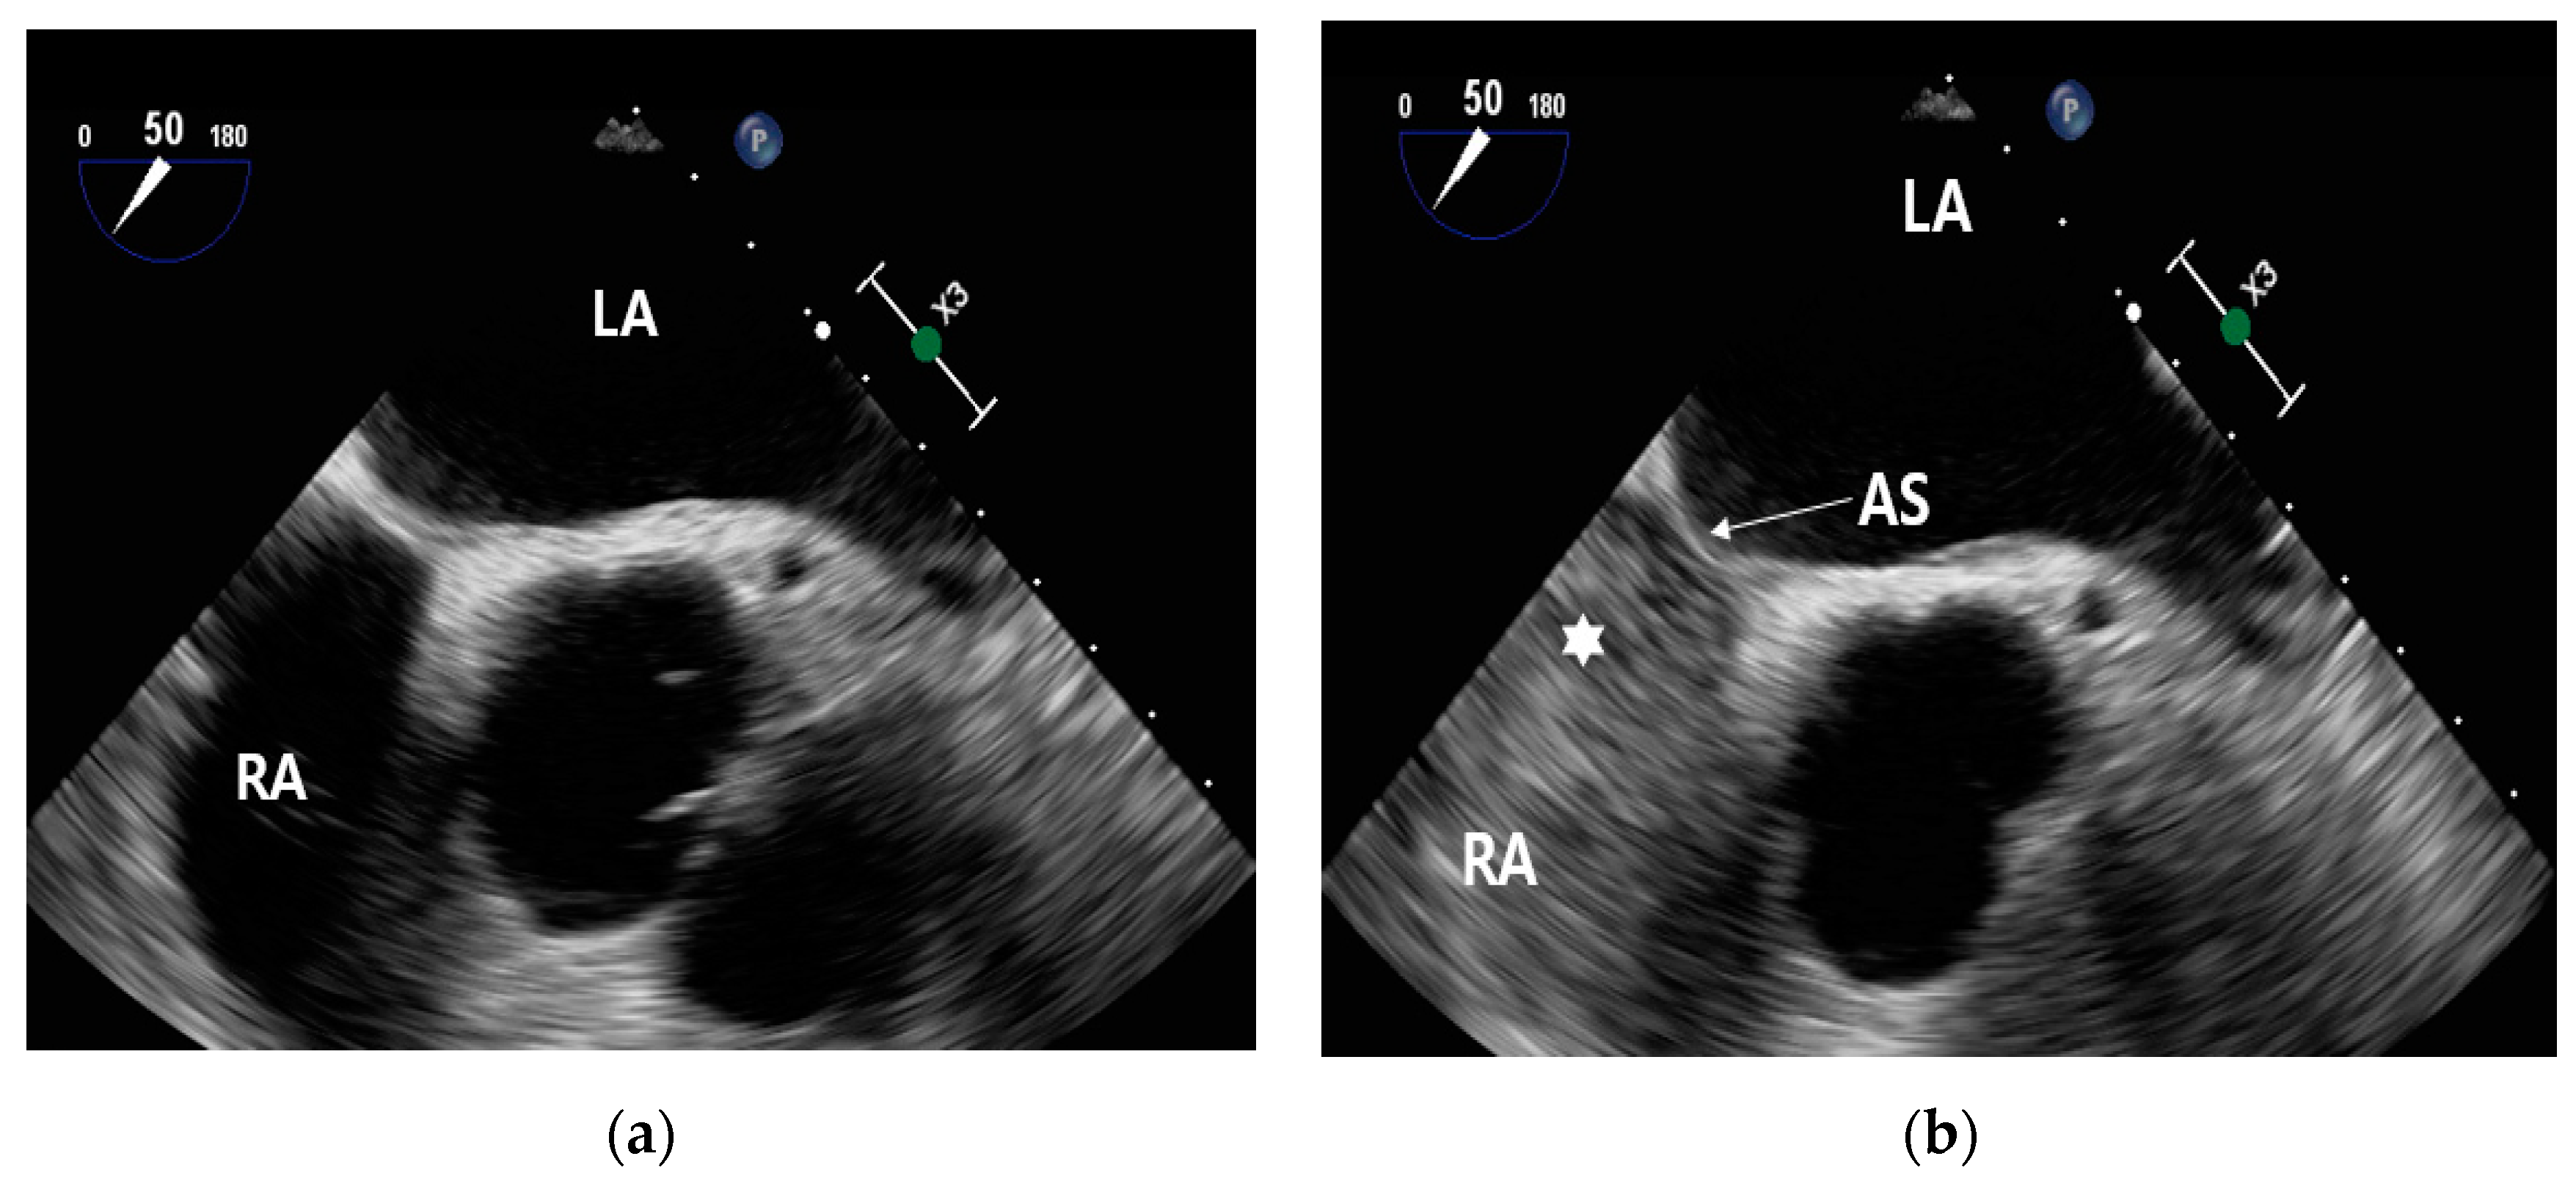

Before the injection of contrast, no contrast is visible within the right atrium (Figure 7(a)). Following the administration of contrast, it becomes evident that the right atrium is now filled with contrast (Figure 7(b)).

Figure 7. Contrast enhancement in the right atrium: Pre- and post-injection observations (a) microbubble pre-contrast injection and (b) filled with microbubble contrast (★) in the right atrium.